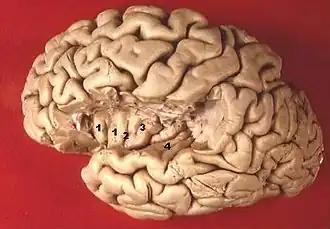

Human brain view on transverse temporal and insular gyri (gyri temporales transversi are #4) | |